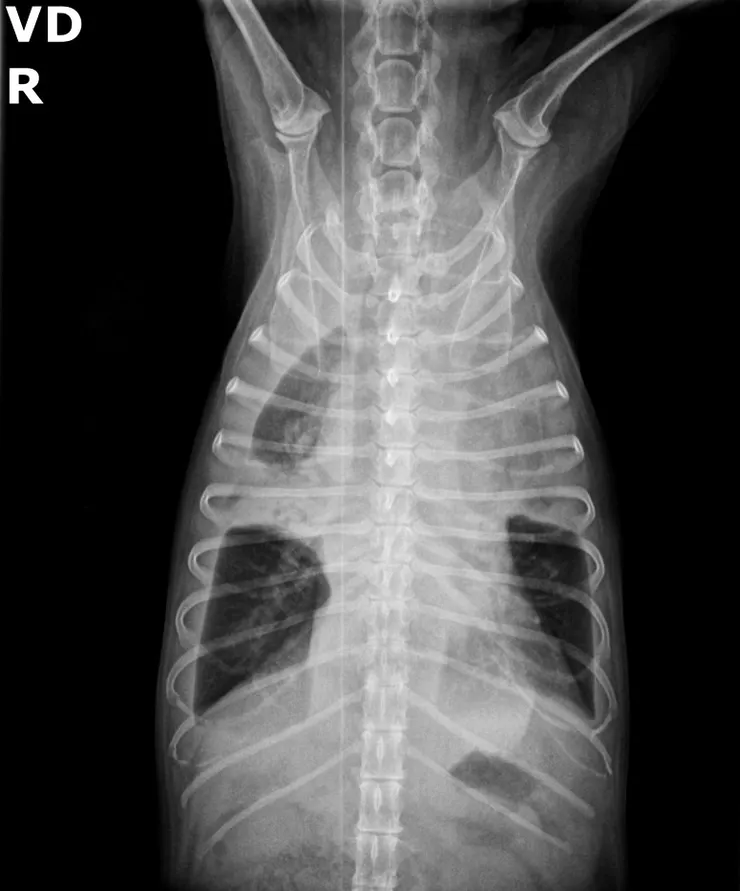

今年這篇研究中統計了十年來被診斷膿胸的狗狗跟貓貓,文獻中透過醫療中發現的證據將造成的原因大略的分成異物/肺部疾病/全身性疾病以及最後都找不到的病因未知等四個大類,並且統整了細菌培養的結果及抗生素的選用。

- 同時出現的氣胸、肉芽腫性胸膜炎及分離出放線菌都能增加吸入異物的懷疑